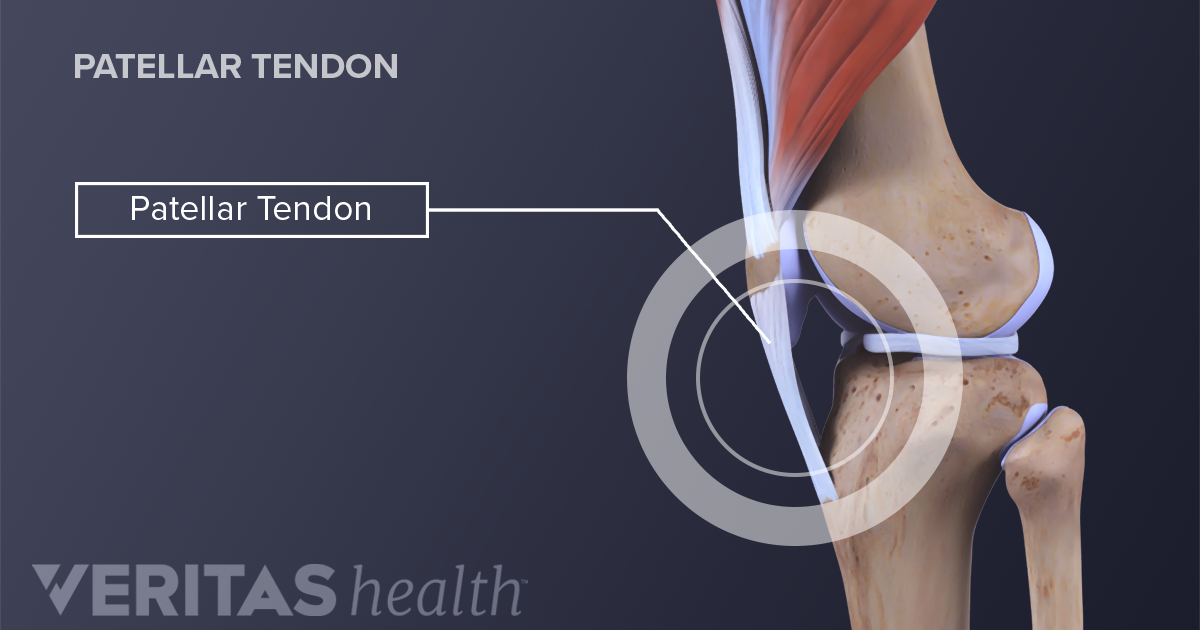

Patellar Fractures (Broken Kneecap

Patellar Fractures (Broken Kneecap